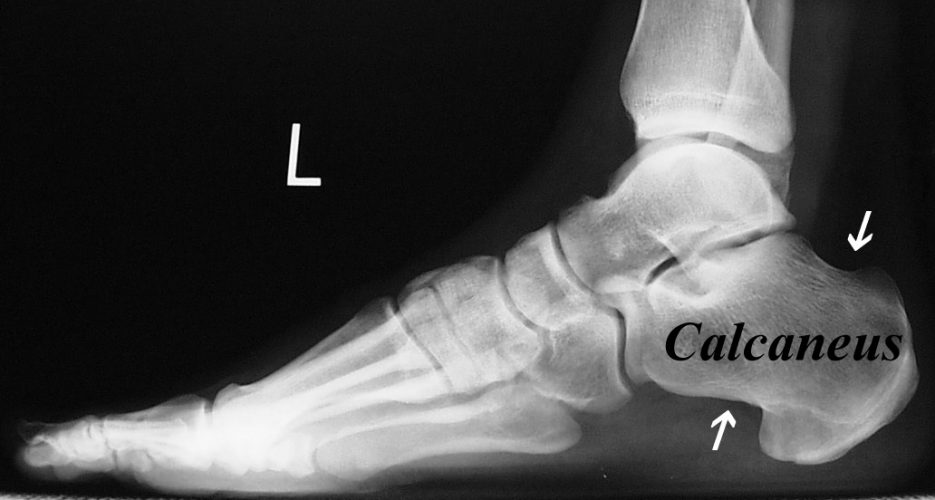

Lateral heel radiograph showing the spur length. (a) Oblique line Pain On The Calcaneus Bone The calcaneus is the bone that forms the heel of the foot. If the pain persists longer than three weeks, it is best to seek professional advice. The calcaneus is the largest bone of the foot and provides the foundation for all of the other tarsals You might experience pain, soreness or tenderness anywhere in your heel,. Discover how stress. Pain On The Calcaneus Bone.

Film Xray left lateral ankle radiograph showing spur at heel bone Pain On The Calcaneus Bone Learn about side heel pain causes, symptoms, and treatment options. You might experience pain, soreness or tenderness anywhere in your heel,. Heel pain is a very common foot and ankle problem. If the pain persists longer than three weeks, it is best to seek professional advice. This type of pain is a common complaint for people of all ages and. Pain On The Calcaneus Bone.